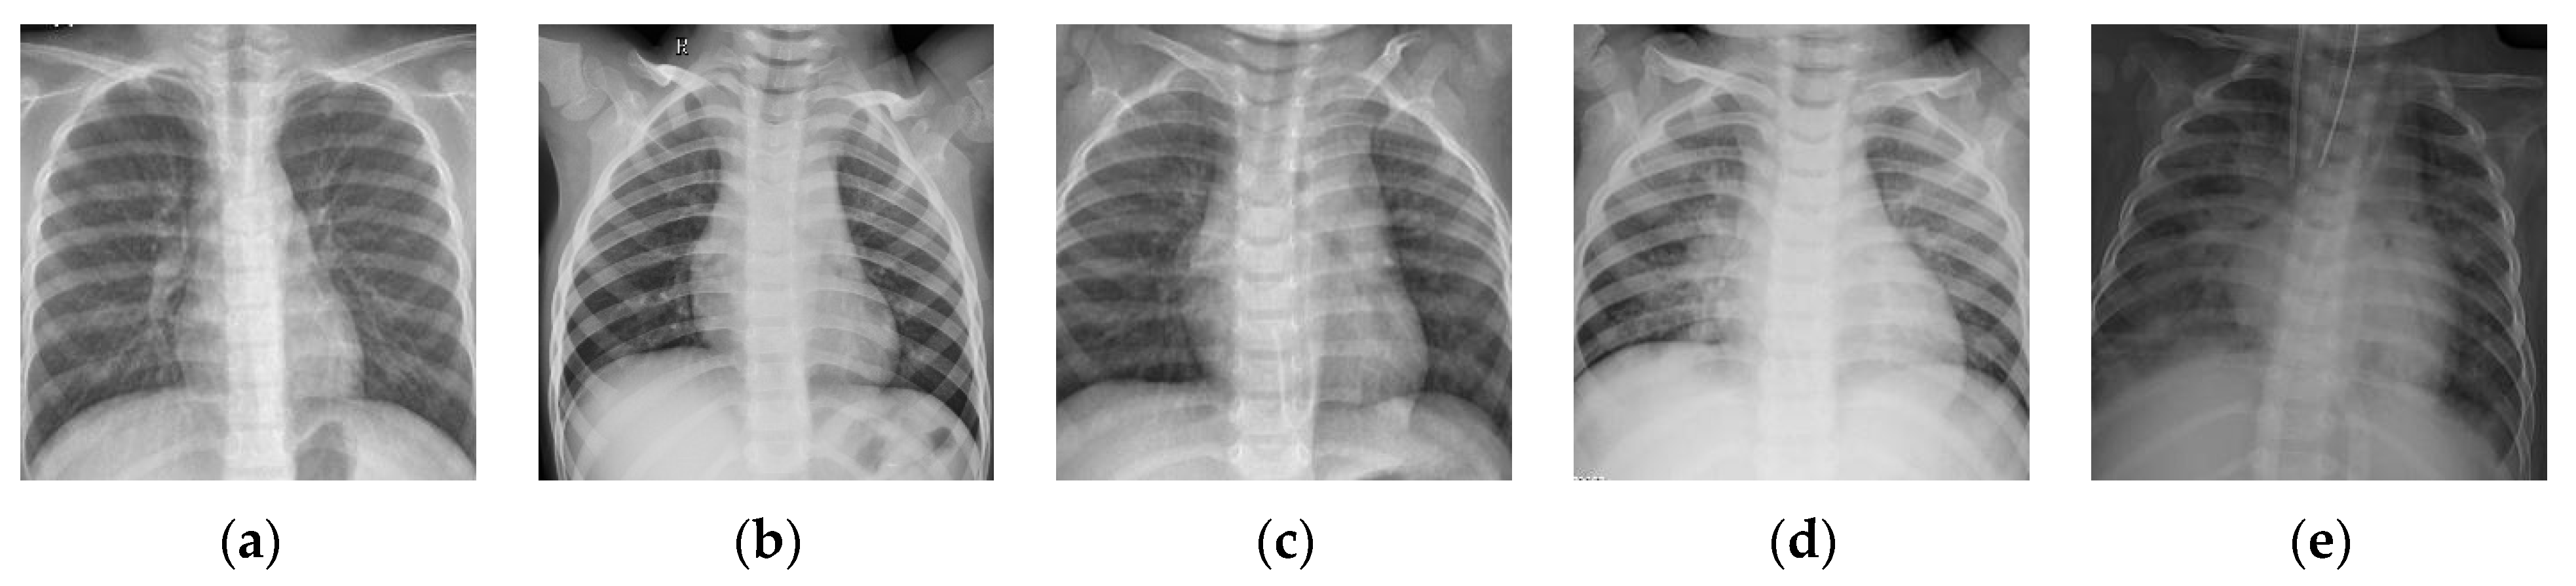

Figure 4.

Examples of the Chest-1 dataset. (a) Normal; (b,c) pneumonia; (d,e) COVID-19.

3.2. The Influence of

The number of images in one batch is an important parameter in the calculation of the BSTriplet loss, because it can influence the similarity matrix and further affect the estimation for training data distribution. Besides this, it has an impact on the stability of the training process. To explore the influence of , we have downloaded a dataset of chest X-ray images [41,42] from the Kaggle [43] website. This dataset is denoted as “Chest-1” for brevity in the following. For this dataset, the X-ray images will be classified into three classes, including normal, (regular) pneumonia, and COVID-19. Several examples are shown in Figure 4. Here, these images are cropped to squares for better clarity. All the images are resized as to be input into the network, and the construction of the Chest-1 dataset is shown in Table 2. According to the data mining strategy described above, we cluster the images in the Chest-1 dataset into six groups by K-means [44], wherein there are two groups for each class. Based on the ratios of groups, we have sampled each group to build different sizes of input batches . ModbileNet-V3-Small is used as the base framework and is trained by CE loss combined with the proposed BSTriplet loss. Some experiments have been performed with various , while other hyper-parameters are fixed according to the method of controlling variables. The accuracy () is adopted as a metric to evaluate the performance, which is defined as: